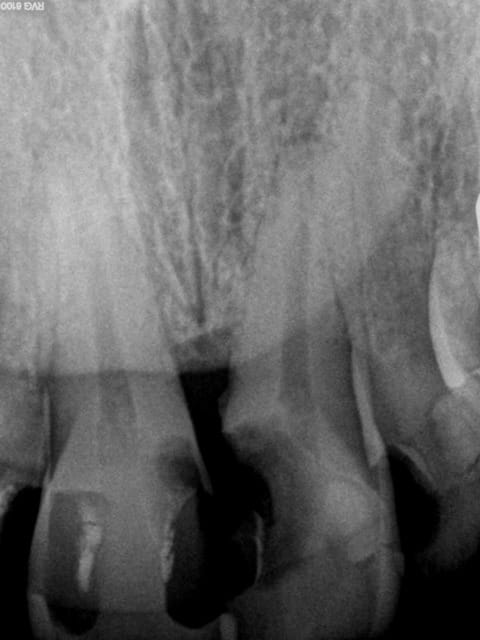

1 sptqqv - Eugenol

2 nrsxww - Eugenol

3 bfr6il - Eugenol

4 yt2f3q - Eugenol

5 rrqwkd - Eugenol

6 nvk9i8 - Eugenol

7 dpigl1 - Eugenol

8 z4bnp9 - Eugenol

9 ad2u4i - Eugenol

10 tgnepm - Eugenol

11 kxxmfo - Eugenol

Endos sans digue, avec de la carie résiduelle, la gutta/ciment ne remplit pas toute la lumière du canal, pas de respect de l'espace biologique, effet férule minimaliste.....

Vu les autres dents le patient ne mérite peut être pas mieux et l'indication est là mieux posée, mais tu te positionnes comme un pro de l'endo puisque tu en ferais souvent et là, c'est pas flagrant...